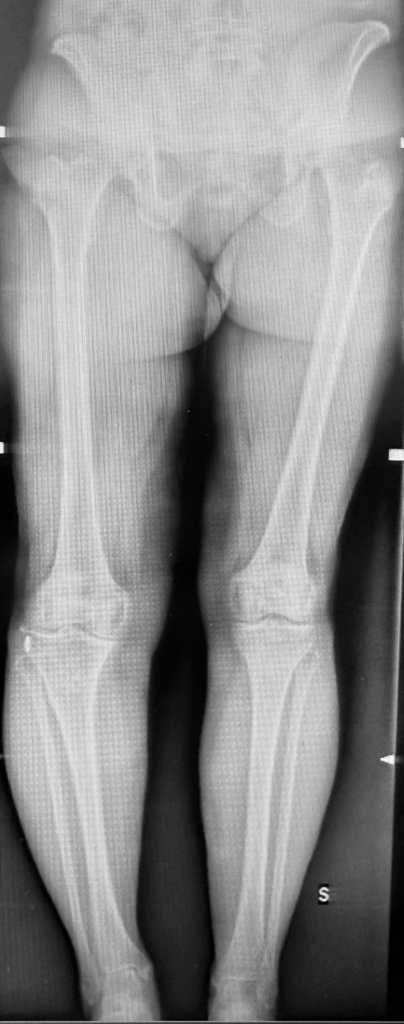

- Radiografie in carico: l’esame fondamentale per valutare in modo indiretto (“quanto si avvicinano le ossa”) l’usura dei tessuti molli. Nei casi più avanzati di coinvolgimento osseo, la valutazione dell’artrosi è diretta e non serve nessun altro esame. Se preferite venire in visita con esami già disponibili, fatevi prescrivere dal vostro medico: 1-RX ginocchia in carico secondo Rosenberg 2-RX latero laterale a condili sovrapposti a 30° di flessione 3-Rx assiali rotulee 30° di flessione 4- RX arti in toto in carico cod.88291